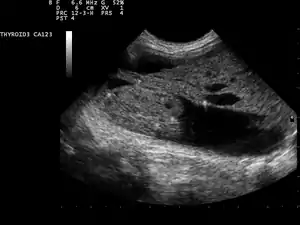

Ultrasound artifacts showing a "comet tail" from a colloid nodule indicate a benign nodule

Ultrasound imaging is useful as the first-line, non-invasive investigation in determining the size, texture, position, and vascularity of a nodule, accessing lymph nodes metastasis in the neck, and for guiding fine needle aspiration cytology (FNAC) or biopsy. Ultrasonographic findings will also guide the indication to biopsy and the long term follow-up.[10] High frequency transducer (7–12 MHz) is used to scan the thyroid nodule, while taking cross-sectional and longitudinal sections during scan. Suspicious findings in a nodule are hypoechoic, ill-defined margins, absence of peripheral halo or irregular margin, fine, punctate microcalcifications, presence of solid nodule, high levels of irregular blood flow within the nodule[11] or "taller-than-wide sign" (anterior-posterior diameter is greater than transverse diameter of a nodule). Features of benign lesion are: hyperechoic, having coarse, dysmorphic or curvilinear calcifications, comet tail artifact (reflection of a highly calcified object), absence of blood flow in the nodule, and presence of cystic (fluid-filled) nodule. However, the presence of solitary or multiple nodules is not a good predictor of malignancy. Malignancy is only diagnosed when ultrasound findings and FNAC report are suggestive of malignancy.[11] The TI-RADS (Thyroid Imaging Reporting and Data Systems) are sonographic classification systems which describe the suspicious findings of thyroid nodules.[12] It was first proposed by Horvath et al,[13] based on the BI-RADS (Breast Imaging Reporting and Data System) concept. Several systems were subsequently proposed and adopted by international scientific societies. Their main aims are to characterize the risk of malignancy of nodules to better select nodules to submit to fine-needle aspiration cytology.[14] Another imaging modality, which is ultrasound elastography, is also useful in diagnosing thyroid malignancy especially for follicular thyroid cancer. However, it is limited by the presence of adequate amount of normal tissue around the lesion, calcified shell around a nodule, cystic nodules, coalescent nodules.[15]